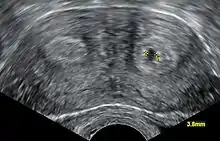

| A human bicornuate uterus | |

Diagnosis of bicornuate uterus typically involves imaging of the uterus with 2D or 3D ultrasound, hysterosalpingography, or magnetic resonance imaging (MRI). On imaging, a bicornuate uterus can be distinguished from a septate uterus by the angle between the cornua (intercornual angle): less than 75 degrees in a septate uterus, and greater than 105 degrees in a bicornuate uterus. Measuring the depth of the cleft between the cornua (fundal cleft) may also assist in diagnosis; a cleft of over 1 centimetre (0.39 in) is indicative of bicornuate uterus.[2]